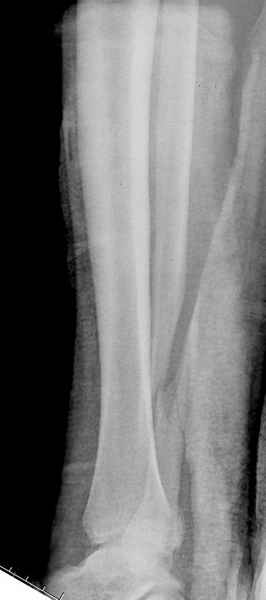

Здесь похожий случай трехнедельной давности, перелом почти сросся и была укорочена малоберцовая, на операции длину малоберцовой смогли восстановить только после того, когда проксимальнее пластины ввели шуруп и использовали его как толкатель, с помощбю дистракционого инструмента (lamina spreader).

Меньше всего волнует положение медиальной лодыжки - в любое время можно провести остео или реостеосинтез, при несращении можно просто резецировать без ущерба для движений в голеностопе. Здесь обошлись фиксацией одним 4 мм канюлированным шурупом.